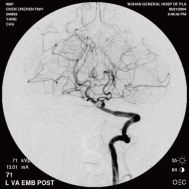

颈内动脉创伤性假性动脉瘤覆膜支架治疗前后(三维像是术前) 右侧颈内动脉后交通动脉瘤栓塞术后完全闭塞